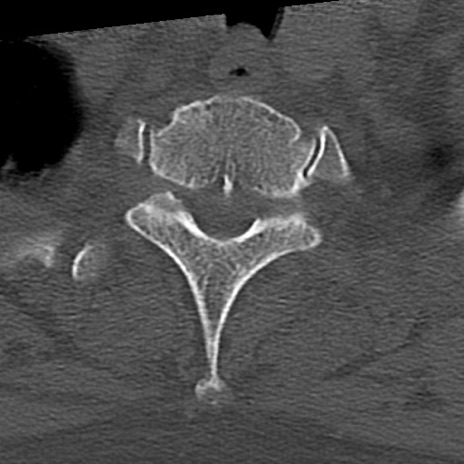

頚椎CT

横断像